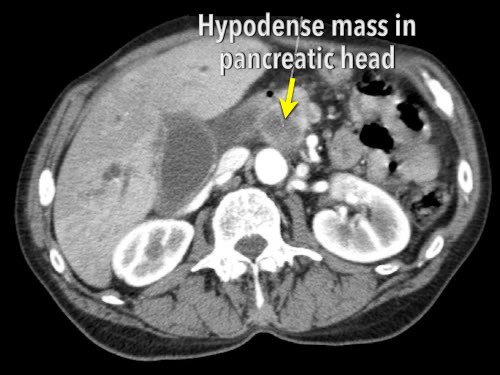

65% ung thư biểu mô tuyến tụy nằm ở đầu tụy, 15% ở thân tụy và 10% ở đuôi tụy. 10% còn lại là đa ổ hoặc lan tỏa (hình).

Khối u ở đầu tụy thường biểu hiện sớm hơn do vàng da tắc mật. Khối u ở thân và đuôi tụy thường biểu hiện muộn và có tiên lượng xấu hơn.

Ung thư biểu mô tuyến tụy thường biểu hiện là một khối giảm tỷ trọng, kém mạch máu, được nhận thấy rõ nhất ở thì động mạch muộn. Đây cũng là thì tốt nhất để đánh giá giải phẫu động mạch nhằm phát hiện các biến thể và hẹp mạch.